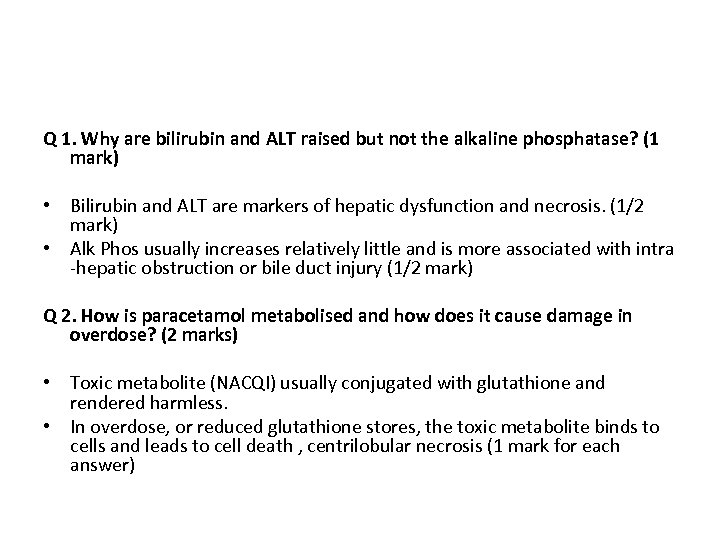

Q 1. Why are bilirubin and ALT raised but not the alkaline phosphatase? (1 mark) Q 2. How is paracetamol metabolised and how does it cause damage in overdose? (2 marks)

Q 1. Why are bilirubin and ALT raised but not the alkaline phosphatase? (1 mark) • Bilirubin and ALT are markers of hepatic dysfunction and necrosis. (1/2 mark) • Alk Phos usually increases relatively little and is more associated with intra -hepatic obstruction or bile duct injury (1/2 mark) Q 2. How is paracetamol metabolised and how does it cause damage in overdose? (2 marks) • Toxic metabolite (NACQI) usually conjugated with glutathione and rendered harmless. • In overdose, or reduced glutathione stores, the toxic metabolite binds to cells and leads to cell death , centrilobular necrosis (1 mark for each answer)